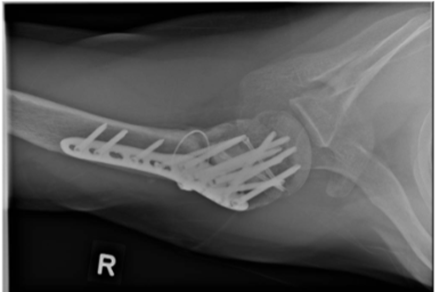

Image 4. 5: Month follow-up radiograph of the right shoulder demonstrating bridging callus and bony union.

A. Anteroposterior (AP) view

B. Valpeau view

C. Lateral/ Y scapula view

The patient followed a structured rehabilitation program that progressed in alignment with key postoperative milestones (Table 1). Pendulum exercises were initiated in the early phase (week 3 post-op) to promote gentle mobility while respecting non-weight-bearing precautions.[33] By week 7, the patient progressed to passive and active-assisted ROM exercises, with particular emphasis on external rotation (Image 6) and flexion (Image 7) using cane-assisted techniques. [33,34] At this stage, the patient also returned to light-duty work. Due to reported stiffness during daily activities, external rotation mobility (Image 8) was further emphasized at the 3-month review. At week 12, the patient initiated active ROM with light resistance, including anterior press and pulley-based exercises. To address his persistent motion limitations, glenohumeral joint mobilization was introduced [35]. Radiographs at 5 months post-operation (Image 4) confirmed bony union, and by week 23, the patient had achieved full functional recovery, resumed cycling and daily activities, with continued education to avoid high overhead movements in view of rotator cuff muscle repair.

Postoperatively, the patient was started on pendular exercises for 6 weeks. before increasing to passive ROM at the postoperative 7 week. He was seen regularly at postoperative 2 weeks, 7 weeks, 3 months and 5 months. Patient returned to work while being placed on light duty at postoperative 7 weeks. On review at postoperative 3 months, there was an increased focus on external rotation range of motion exercises due to shoulder stiffness reported by the patient during daily activities. Bony union was observed on radiographs taken at postoperative 5 months (Image 4).